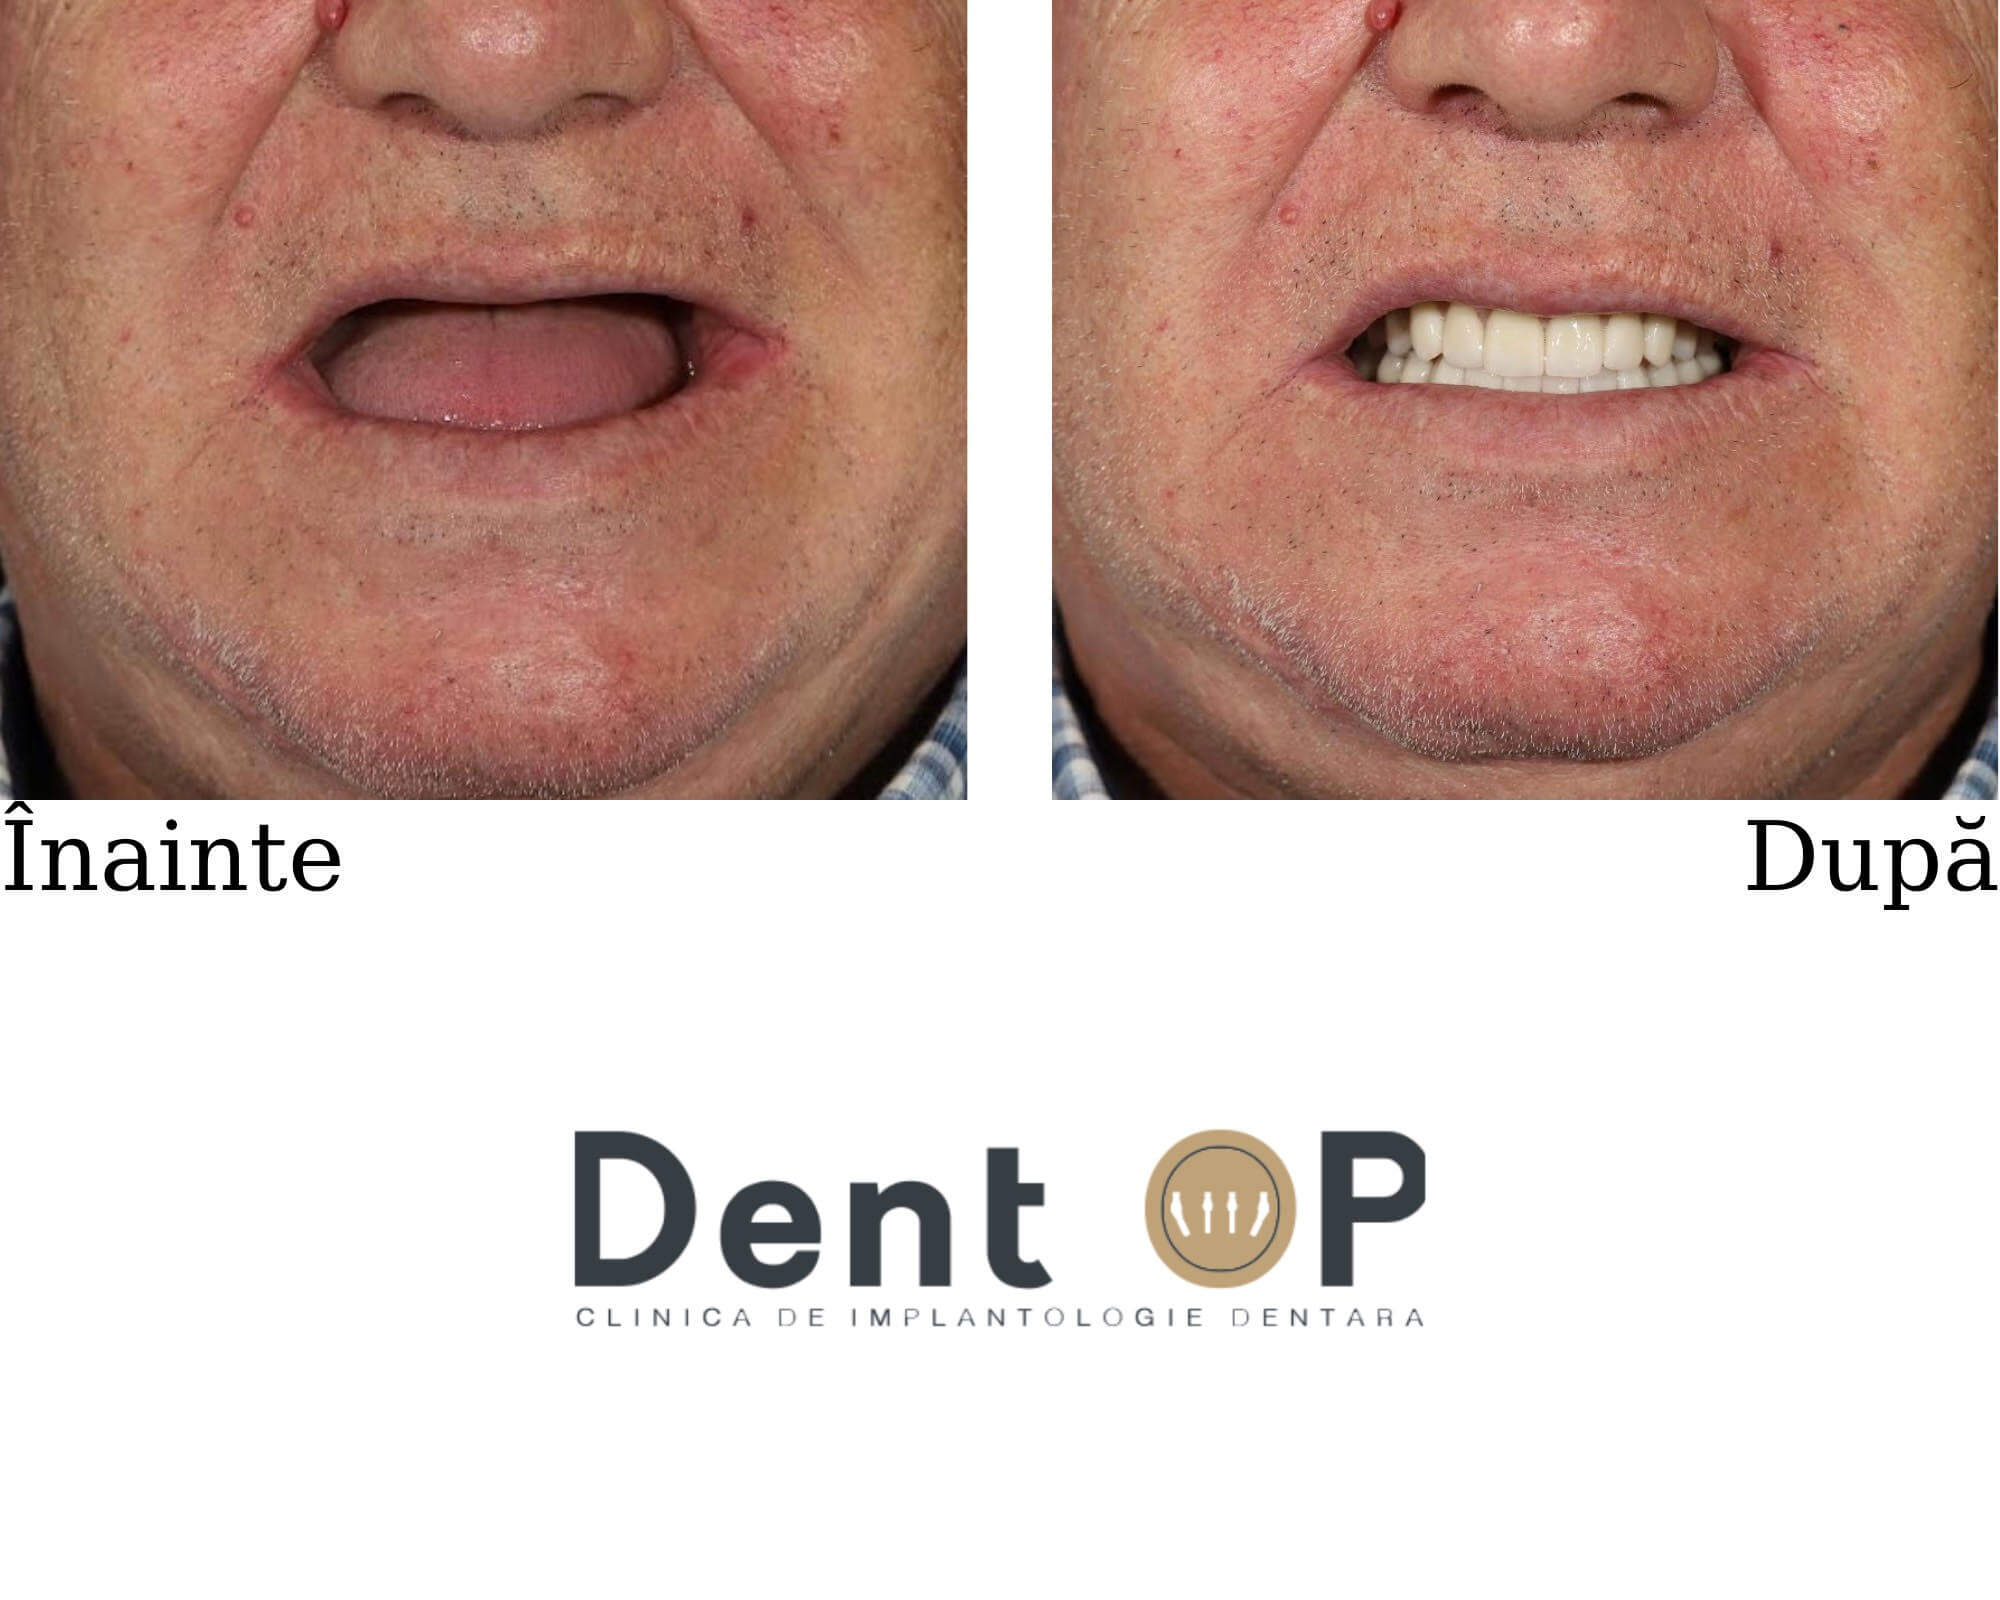

Boala parododontală agresivă i-a distrus dantura, dar procedura ,,Dantură Fixă în 24h pe implanturi dentare” i-a salvat încrederea de sine și zâmbetul. Domnul T. a trecut printr-o intervenție complexă de inserare a 10 implanturi dentare într-o singură ședință.

Încă de la prima consultație, Dr Cazacu Corrado a decis extragerea tuturor dinților rămași care erau afectați și inserarea de implanturi dentare pe care să stea apoi o lucrare fixă.În radiografia de mai jos vom observa dantura pacientului înainte și după ce au fost inserate cele 10 implanturi dentare atât la maxilar cât și la mandibulă.

După 24h de la intervenție, domnul T. s-a prezentat din nou la clinică pentru a-i fi fixate lucrările provizorii, lucrări pe care le-a purtat timp de 4-6 luni și care l-au ajutat să mănânce și să zâmbească.

După această perioadă, pacientului i-au fost fixate lucrările finale, lucrări concepute special pentru fizionomia sa. La alegerea acestora, domnul T. și-a exprimat preferințele și nevoile legate de aspectul final al dinților.